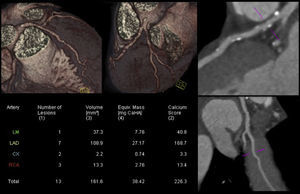

In addition, and also of considerable importance, recent technological developments in scanner technology (both hardware and software) have led to impressive reductions in radiation dose, the main limitation of CCTA.72,73Figure 7 presents an example of a CCTA performed with a new-generation scanner, showing high image quality with ultra-low radiation and contrast doses (0.5 mSv and 50 cc, respectively).

Coronary computed tomography angiography of a non-competitive athlete performed with a new-generation scanner (SOMATOM Force, Siemens Healthcare), using an ultra-low radiation dose of 0.5 mSv. Left: volume rendering technique images and study protocol; middle: nonobstructive mixed plaque in the proximal segment of the right coronary artery; right: nonobstructive calcified plaque in the proximal left anterior descending artery. LAD: left anterior descending artery; RCA: right coronary artery.